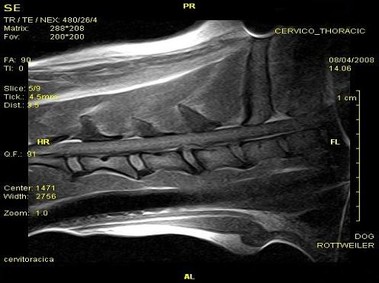

В настоящее время МРТ является наиболее предпочтительным методом визуализации любых мягких тканей, особенно для визуализации травм и патологий центральной нервной системы и суставов. Особенности Vet-MR позволяют использовать данный метод визуализации также в сфере ветеринарии.

Vet-MR специально разработана для визуализации небольших животных и является результатом внимания к деталям при разработке магнита, катушки и электронных компонентов, обеспечивая высокое качество экономически эффективной и простой в использовании МРТ в сфере ветеринарии.